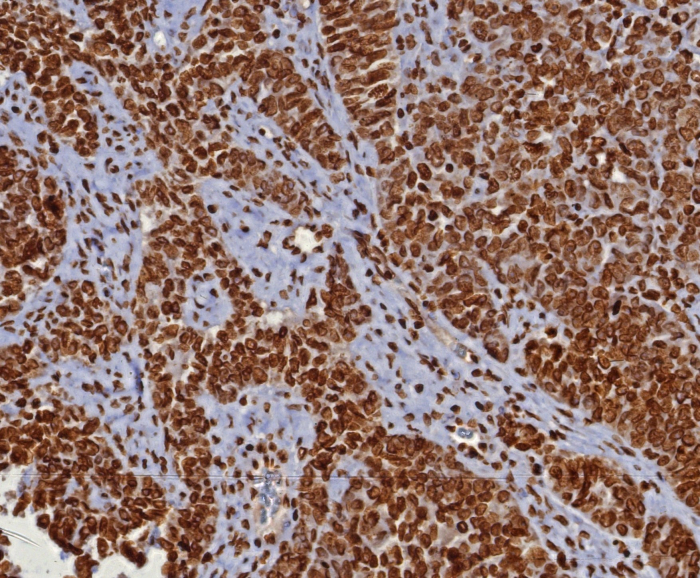

Formalin-fixed, paraffin-embedded human ovarian cancer (serous) stained with dsDNA antibody (DSD/8204R). HIER: Tris/EDTA, pH9.0, 45min. Secondary: HRP-polymer, 30min. DAB, 5min.

Formalin-fixed, paraffin-embedded human placenta stained with dsDNA antibody (DSD/8204R). HIER: Tris/EDTA, pH9.0, 45min. Secondary: HRP-polymer, 30min. DAB, 5min.

This monoclonal antibody recognizes the double stranded DNA in human cells It can be used to stain the nuclei in cell or tissue preparations and can be used as a nuclear marker in human cells This monoclonal antibody produces a homogeneous staining pattern in the nucleus of normal and malignant cells

Immunohistochemistry (Formalin-fixed): 1-2ug/ml for 30 minutes. at RT. Staining of formalin-fixed tissues requires heating tissue sections in 10mM Tris with 1mM EDTA, pH 9.0, for 45 min at 95C followed by cooling at RT for 20 minutes.